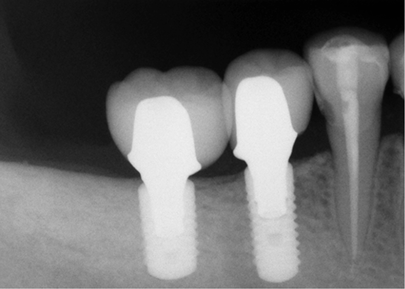

Replace teeth that have been lost with the passage of the years restoring functionality and aesthetics to your mouth.A dental implant is a cylinder shaped dental root manufactured alloplastic material (usually titanium) which is surgically implanted under the gums inside the maxillary or mandibular bone; once placed and osseointegrated, the dentist will place upon them crowns or fixed bridges that will replace the teeth lost, then the implant helps us provide retention and support a fixed or removable dental prosthesis.

Consists on the placement of the dental implant, osseointegration (period of two or three months), and their subsequent rehabilitation (placement of the prosthesis).

In Dental Evolution in Cancun, our specialists evaluate your particular case by taking photographic records, prints, lateral x-ray of the skull and orthopantomography, enabling us to study the craniofacial structure and your maxillomandibular relationship, in order to determine your oral health, since it is very important to have healthy gums and adequate bone that supports the Dental Implant.